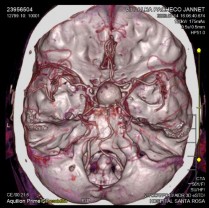

Estudios imagenológicos: los estudios tomográficos indicaron aneurisma sacular de la arteria carótida interna supraclinoidea derecha asociado a remodelación ósea (Figuras 1 y 2). Mientras que la resonancia magnética nuclear (RMN) de hipófisis mostró dilatación sacular aneurismática que ocupa la silla turca con extensión supraselar, dependiente de la arteria carótida derecha.

Figura 2 Reconstrucción angiotomográfica cerebral. Las medidas aproximadas fueron de 20,6 x 1,6 x 16,7 mm en sus diámetros anteroposterior, transversal y craneocaudal. Existió ocupación de silla turca y formación de arteria carótida interna derecha.